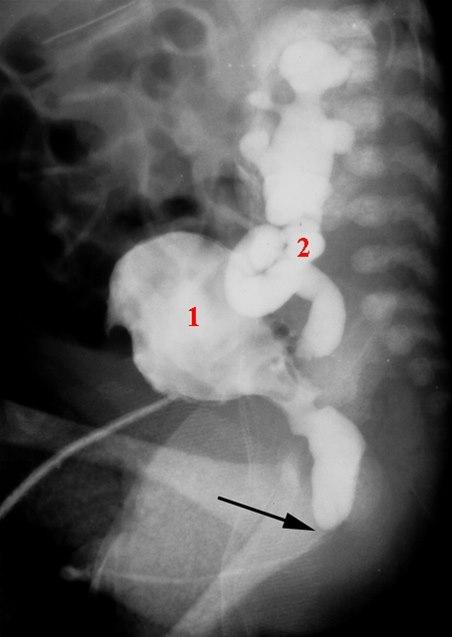

Miksjonscystografi, sidebilde

Klaff i urinrør (pil) som har medført utvidelse av urinrøret over klaffen, fortykket urinblærevegg og urin-reflux til en utvidet og slynget urinleder

Kontrasten er satt inn gjennom et suprapubisk kateter

- Urinblære

- Ureter